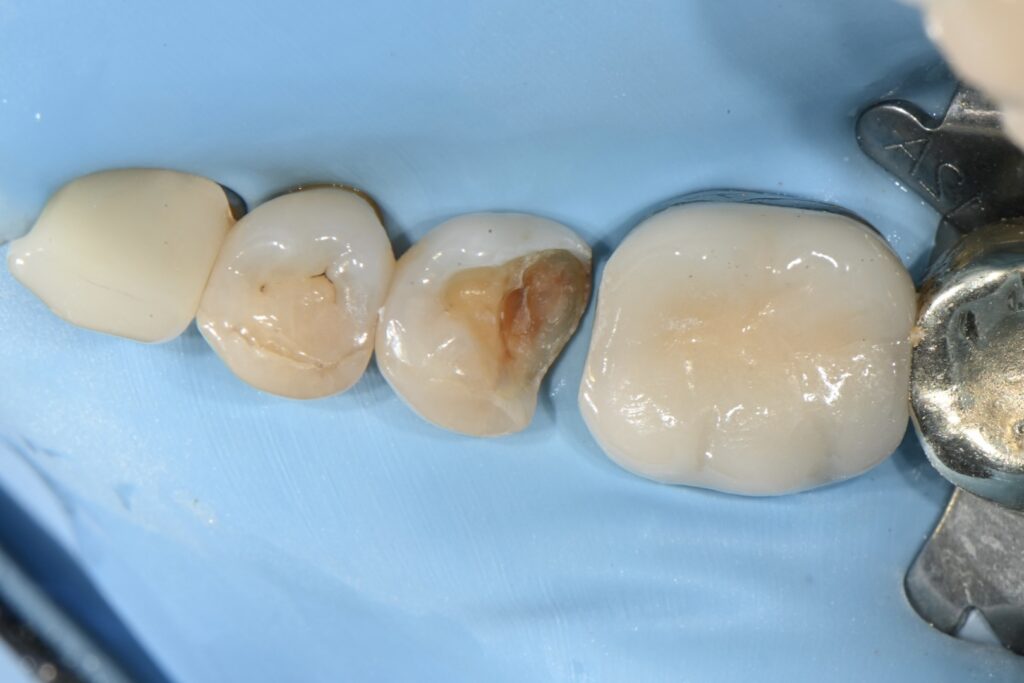

레진 빌드업의 필수 러버댐의 적용

레진빌드업의 필수 바로 러버댐의 적용입니다

여러가지 원인 세균의 감염 타액의 침투 등등

다양한 원인으로 인하여 러버댐이라는 건 필수인데요

이 하늘색 시트지가 러버댐이라는 시트입니다

세균감염을 예방하고 그리고 타액을 들어오지 못하게 하는

아주 중요한 부분입니다

여기에서 뒷쪽 깍인부분을 재건하려면 매트릭스라는 것들이 필요한데요

다양한 매트릭스중 치아의 외형을 잘 재현하는

그리고 인접면을 잘 만들어 주어야

그래야만 음식물이 끼이는걸 방지할 수 있습니다

점점 치아의 형태를 만들어 가는 과정입니다

여기서 정확히 접착이 이루어지기 때문에(러버댐 및 철저한 방습 그리고 주입식 몰드 레진 팩킹) 완전한 강도의 치아 형태를 만들어 갈 수 있습니다.